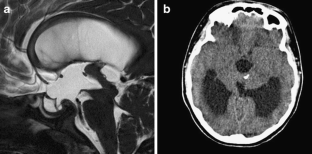

The sylvian aqueduct is the most common site of intraventricular blockage of the cerebro-spinal fluid. Clinical aspects, neuroradiological appearance, and treatment of hydrocephalus secondary to aqueductal stenosis are specific.

The correct interpretation of the modern neuroradiologic techniques may help in selecting adequate treatment between the two main options (third ventriculostomy or shunting). In the last decades, endoscopic third ventriculostomy has become the first-line treatment of aqueductal stenosis; however, some issues, such as the cause of failures in well selected patients, long-term outcome in infant treated with ETV, and effect of persistent ventriculomegaly on neuropsychological developmental, remain unanswered.